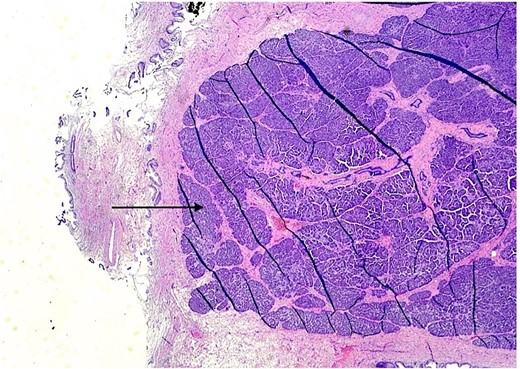

The patient underwent an elective laparoscopic cholecystectomy. During the surgery, findings were consistent with chronic cholecystitis. No abnormalities were visible upon gross inspection. Postoperatively, the patient recovered well and was discharged on the same day. The macroscopic histopathological examination revealed an intact GB with pink serosa. The mucosa was yellow-red without focal lesions. The microscopy showed chronic cholecystitis and the presence of a 1 cm focal nodule in the GB wall compatible with ectopic pancreatic parenchyma containing only acinar and ductal components (Figs 2–3). There was no evidence of dysplasia or malignant transformation in the analyzed sections. Since no malignancy was found among the EPT, there was no need for further treatment.

H & E stain 20×: Ectopic pancreatic parenchyma, composed of ductal and acinar components (black arrow).